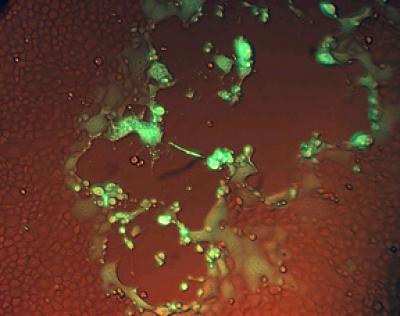

Cornell microbiologists have shown that a single amino acid variation in an enzyme that is part of the DNA copying process of equid herpesvirus type 1 (EHV-1) creates a different type of EHV-1, which causes the neurological disorders in horses. Both types of EHV-1 can also cause abortions.

After cloning the genome of the virus obtained from a mare that had both lost a fetus and developed neurological symptoms, the researchers then altered one amino acid in the viral enzyme known as DNA polymerase and rendered the virus unable to cause neurological disease. The amino acid change reduced levels of the virus in the horse's bloodstream, and low levels of the virus reached the central nervous system. The mutation also made the virus more susceptible to antiviral drugs. The researchers believe the reduced replication and levels of virus in the blood may be why one form of the virus does not cause neurological disorders.